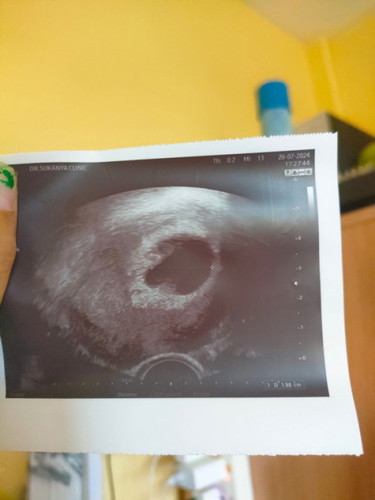

เจอถุงตั้งครรภ์ไม่เจอตัวอ่อน

เจอถุงตั้งครรภ์ไม่เจอตัวอ่อน#ขอบคุณล่วงหน้าสำหรับความคิดเห็นค่ะ แม่ๆบ้านไหนมีประสบการณ์ท้องลม หรือไม่ตรวจยังไม่เจอตัวอ่อนบ้างคะ เจอน้องตอนกี่วีคกัน กังวลมากหมอบอกอาจเป็นท้องลม ให้ขูดมดลูกเลย แนะนำที เรายังหวังว่าจะได้เจอน้อง #ขอบคุณล่วงหน้าสำหรับความคิดเห็นค่ะ